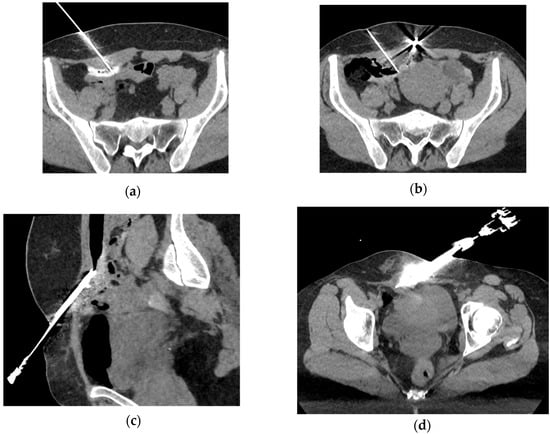

- Welch, B.T.; Ehman, E.C.; VanBuren, W.M.; Cope, A.G.; Welch, T.L.; Woodrum, D.A.; Kurup, A.N.; Burnett, T.L. Percutaneous cryoablation of abdominal wall endometriosis: The Mayo Clinic approach. Abdom. Radiol. 2020, 45, 1813–1817. [Google Scholar] [CrossRef] [PubMed]

- Dibble, E.H.; D’Amico, K.C.; Bandera, C.A.; Littrup, P.J. Cryoablation of Abdominal Wall Endometriosis: A Minimally Invasive Treatment. Am. J. Roentgenol. 2017, 209, 690–696. [Google Scholar] [CrossRef] [PubMed]

- Maillot, J.; Brun, J.L.; Dubuisson, V.; Bazot, M.; Grenier, N.; Cornelis, F.H. Mid-term outcomes after percutaneous cryoablation of symptomatic abdominal wall endometriosis: Comparison with surgery alone in a single institution. Eur. Radiol. 2017, 27, 4298–4306. [Google Scholar] [CrossRef] [PubMed]

- Najdawi, M.; Razakamanantsoa, L.; Mousseaux, C.; Bendifallah, S.; Touboul, C.; Thomassin-Naggara, I.; Bazot, M.; Barral, M.; Cornelis, F.H. Resolution of Pain after Percutaneous Image-Guided Cryoablation of Extraperitoneal Endometriosis. J. Vasc. Interv. Radiol. 2023, 34, 1192–1198. [Google Scholar] [CrossRef] [PubMed]